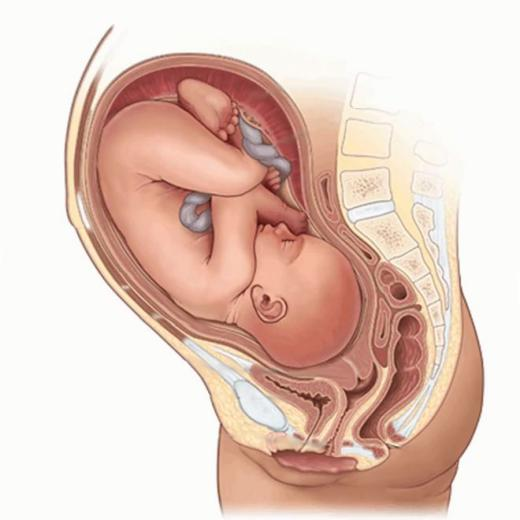

首先大家要知道,宝宝在妈妈肚子里是这样的~

是这样的....

这就是新生儿“鸟巢”式护理的依据~

新生儿“鸟巢式”护理是一种模仿子宫环境的护理方式。使胎儿在外部环境中仍然保持类似母体的卷曲姿势,为新生儿提供一个更加舒缓的过渡阶段,帮助新生儿逐渐消除脱离母体产生的紧张感,为新生儿提供安全感。